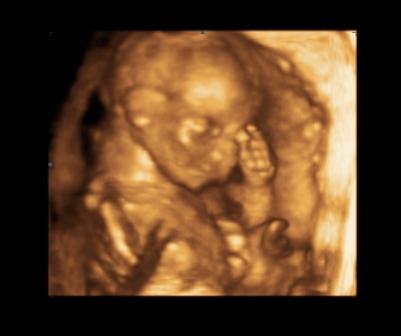

Balimami: fantasztikus a vigyórgó Uh képed!!apa elolvadt mi?

Voltam uh-n Bécsben, és szerencsére minden rendben. NT:1,7mm. A baba szégyenlös volt, és mindíg elfordult, jó sokáig tartott, mire a doktornö meg tudta mérni a nyaki redöt, így kb. 15 percig babamoziztunk. :lol: Hihetetlen aranyos volt, izgett-mozgott, majd befordult aludni, köhögnöm kellett, hogy felébredjen, és pózt váltson. :lol:

Régóta nem írtam, azt hiszem kissé depis vagyok már egy ideje. Ma este voltunk uh-n, végre van kép Kendéről. Remélem sikerül beilleszteni. Na nem hagyta. azt írja túl nagy...

na csak sikerült!!!! :)

Kép Kende baba

Krisz: nagyon cuki babóca :D :wink: és azok a drága kis ujjacskák, zabálnivaló :wink: :D szép formás a kis arca :wink: